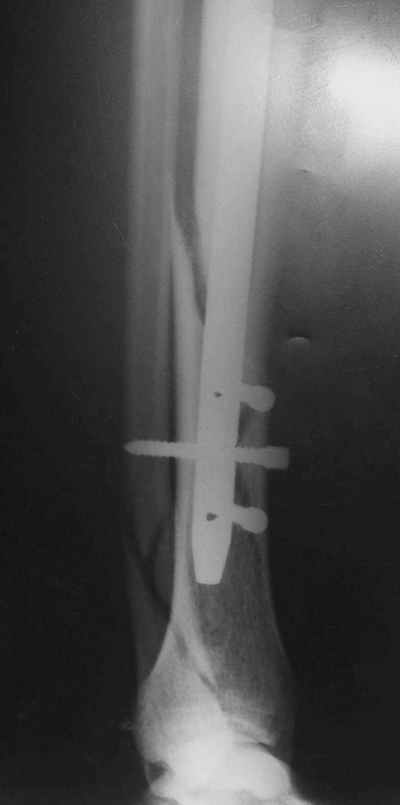

Рентгенограмы

Не удается отправить первичные снимки. А что скажите по имеющимся?!

Выполненный остосинтез нестабилен. Штифт надо заменить по "размеру" на солидный, дистльно три запирающих винта. Успехов!

Перелом спиральный, то есть низкоэнергетический, так что со сращением дело обстоит уже неплохо, лишь бы "костоеда" не развилась. Отломки выглядят уже стабилизированными костной мозолью, так что довводить винты, наверно, уже незачем. Разве что при клинической оценке подвижность еще есть - тогда можно для стабилизации наложить простейший аппарат, не опасаясь контакта его элементов с гвоздем, поскольку места в дистальном метафизе оставлено более чем достаточно.

С Александром согласен, нет необходимости делать дополнительные усилия для сращения, не большая компрессия аппаратом из двух колец и полная нагрузка доделает работу.

Потекли блокирующие винты.

Удалять их всё равно придётся.

Уже имеется какое-то сращение. А в этих условиях выполнить реостеосинтез гвоздём не дольше, чем "накинуть" аппарат из двух колец. Ходить можно сразу с полной нагрузкой, да и качество жизни пациента без аппарата лучше.